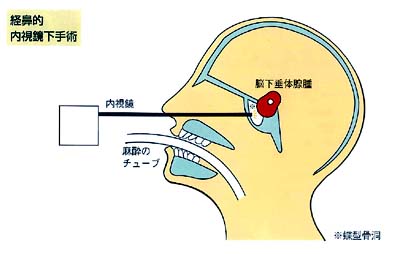

経鼻的内視鏡下手術

最近数年来の傾向として、この経鼻的下垂体手術を内視鏡下に行なう手技が普及・安定してきました。

左右どちらかの鼻孔から内視鏡を蝶型骨洞(前出)直前まで挿入し、ここに小さく粘膜切開と骨窓を作り、内視鏡を蝶型骨洞内に進めこれを固定します。

以後の手技は基本的に顕微鏡の手術と同様ですが、内視鏡手術では手術野が広く明るい上、顕微鏡手術の死角の部分も十分観察できます。

しかし、これはあくまでモニターの画面で見えているだけで、本来到達しにくい場所の腫瘍を摘出するにはかなりの熟練と特殊な手術道具が必要です。

内視鏡手術も全国的に普及してきており、安全かつ確実な手術方法になってきております。